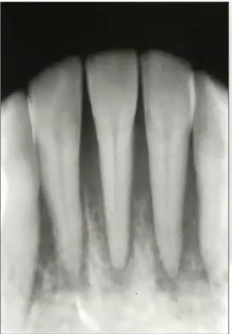

Pano of osteoma

Well circumscribed radiopaque lesion

Radiographic image of osteoma